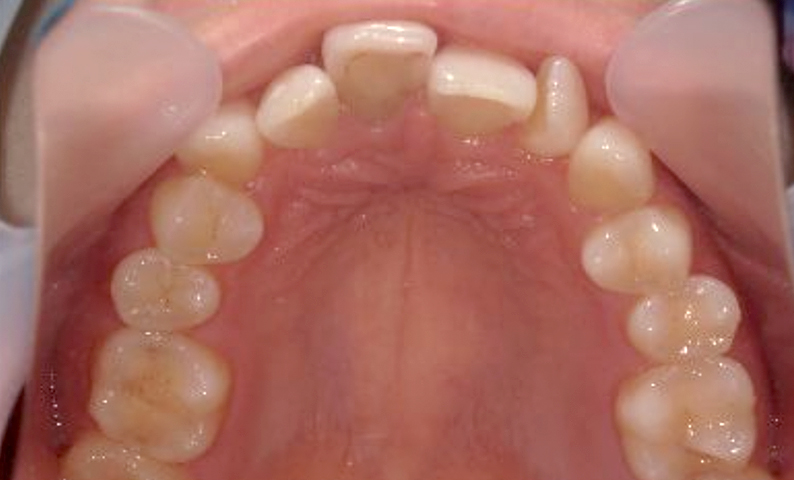

症例_025 上顎だけの部分矯正

治療期間:7ヶ月金額:30万円+税女性前歯のガタガタ上の前歯だけ

| Before | After |